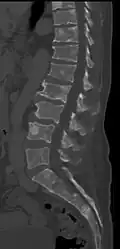

-

Pathological fracture of the lumbar spine due to multiple myeloma -

CT scan of the lower vertebral column in a man with multiple myeloma, showing multiple osteoblastic lesions: These are more radiodense (brighter in this image) than the surrounding cancellous bone, in contrast to osteolytic lesions, which are less radiodense. -